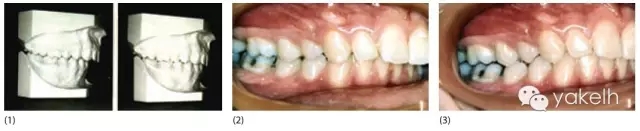

¤¤一些學(xué)者認(rèn)為顱頜功能紊亂與錯(cuò)密切相關(guān),而另一些學(xué)者堅(jiān)稱(chēng)錯(cuò)牙合對(duì)TMD的風(fēng)險(xiǎn)沒(méi)有影響。形態(tài)牙合與功能牙合的區(qū)別是對(duì)這種分歧的一個(gè)解釋。圖15.1的患者是安氏Ⅰ類(lèi)牙合關(guān)系,主訴是肌肉疼痛和緊張性頭痛。當(dāng)該患者戴用平面咬合板時(shí),她的牙合關(guān)系從中性牙合變?yōu)檫h(yuǎn)中牙合。顯然她存在雙重牙合,同時(shí)肌電檢查顯示接位的肌電活動(dòng)強(qiáng)度要顯著高于該患者被要求咬緊牙時(shí)的肌電強(qiáng)度。在這兩個(gè)頜位拍攝的X線片證實(shí)當(dāng)該患者咬合于安氏Ⅰ類(lèi)牙尖交錯(cuò)位時(shí),她的髁突發(fā)生了前下移位,而當(dāng)她試圖建立后退接觸位時(shí),髁突回到關(guān)節(jié)窩正中。我們通常在最大牙尖交錯(cuò)位對(duì)患者進(jìn)行觀測(cè)和記錄,但該頜位不一定代表一個(gè)與功能牙合相協(xié)調(diào)的頜位,這可能是評(píng)價(jià)牙合與TMD相關(guān)性時(shí)的一個(gè)混雜因素。

圖15.1 (1)兩個(gè)不同頜位的研究模型。左側(cè)的模型顯示的是患者被要求將牙齒咬合在一起時(shí),自發(fā)咬合形成的牙合,右側(cè)模型顯示的是患者戴用平面咬合板一段時(shí)間后建立的后退接觸位的咬合。(2,3)相同情況下的臨床表現(xiàn)。